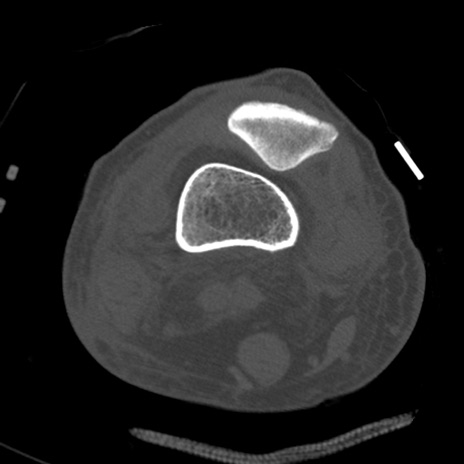

症例28 右膝関節CT(横断像)

右膝関節CT